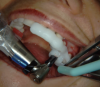

Figure 18. Surgical guide in place for osteotomy surgery.

Figure 15 and Figure 16. 3D scan and plan using R2 gate software (Megagen,www.imegagen.com) and R2 surgical guide.